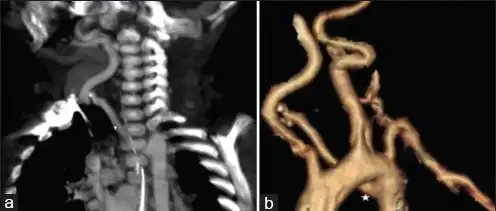

-

CT shows aberrant right subclavian artery -